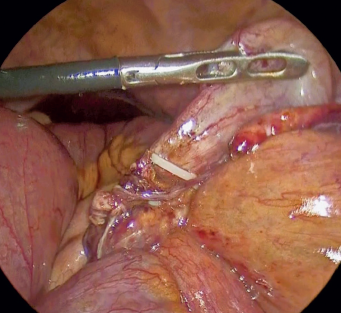

Durante la disección se evidenció que el colapso del asa de íleon fue provocado por un anillo constrictor apendicular causado por el apéndice cecal. Se continuó con la disección hasta localizar la base y la punta apendicular; esta última se encontraba firmemente adherida al íleon (figura 4). Se realizó disección roma de la punta apendicular, logrando separarla del íleon sin lesión en este. Una vez liberada la porción, se revisaron las características de coloración y se corroboró la perfusión con filtro de verde de indocianina (ICG) (figuras 5 y 6).

Imagen: Salinas-García et al.

Figura 5 Imagen laparoscópica que muestra vascularidad adecuada del asa intestinal con verde de indocianina.